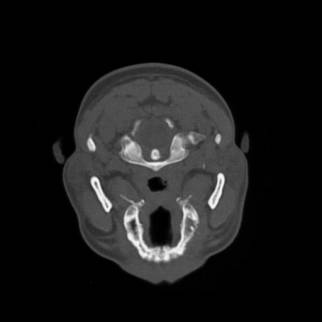

Figura 12 Immagine TAC relativa ad una sezione trasversale del cranio.